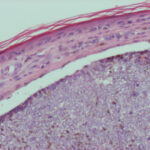

PIGMENTED BASAL CELL CARCINOMA

Pigmented BCC is a sub-type of nodular BCC that exhibits increased melanization. Pigmented BCC appears as a hyperpigmented, translucent papule, which may also be eroded (Fig. 115-3). The differential diagnosis includes nodular melanoma.

Pigmented Basal Cell Carcinoma

Pigmented BCC shows histologic features similar to those of nodular BCC but with the addition of melanin.38 Approximately 75 percent of BCCs contain melanocytes, but only 25 percent contain large amounts of melanin. The melanocytes are interspersed between tumor cells and contain numerous melanin granules in their cytoplasm and dendrites. Although the tumor cells contain little melanin, numerous melanophages populate the stroma surrounding the tumor.